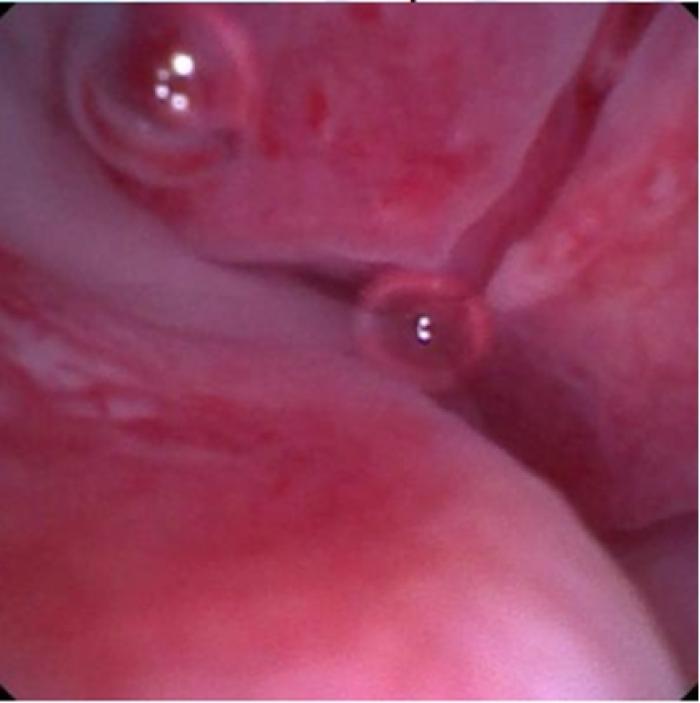

El examen endoscópico reveló inflamación y cambios estructurales severos en los cornetes nasales (más marcados en fosa nasal izquierda) y confirmó la presencia de una estenosis anular fibrosa en la región nasofaríngea media-caudal, con un diámetro luminal estimado de 2 mm. No se identificaron cuerpos extraños ni masas neoplásicas (Figura 4-5; Vídeo 4).

En base a los hallazgos, se planificó y realizó una rinoscopia y nasofaringoscopia retrógrada para confirmar y tratar la alteración, en la que se confirmó la presencia de una estenosis anular fibrosa en la región nasofaríngea media-caudal, con un diámetro luminal estimado de 2 mm, sin identificarse cuerpos extraños ni masas.